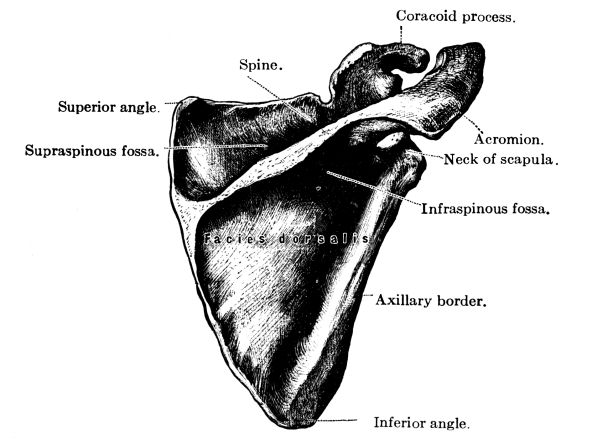

| The Upper Extremities | 171 |

The Shoulder Girdle, 171—The Clavicle, 171—The Scapula, 173—Shoulder Muscles, 174—The Humerus, 175—Upper Arm Muscles, 176—The Ulna, 177—The Radius, 178—The Wrist, 180—The Hand, 181—Meta-carpals, 181—Phalanges, 181—Muscles of the Forearm, 182—Muscles of the Hand, 184—Joints of the Upper Extremity, 185—Blood Supply of the Upper Extremity, 185—Nerves of the Upper Extremity, 186. |